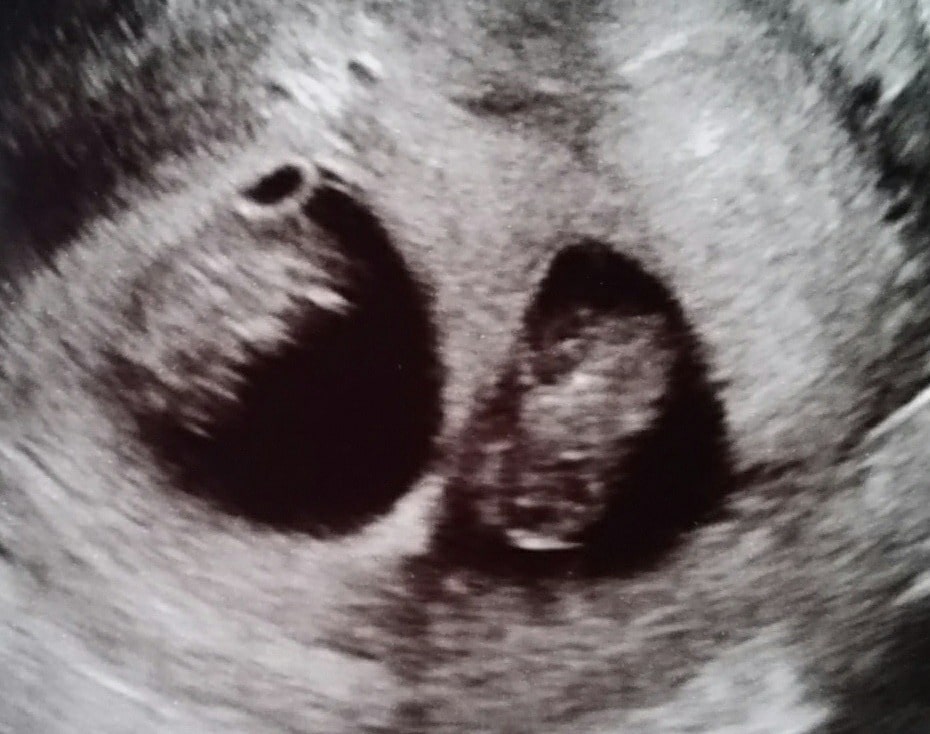

Ultrasound Photos of 10 Weeks Pregnant With Twins